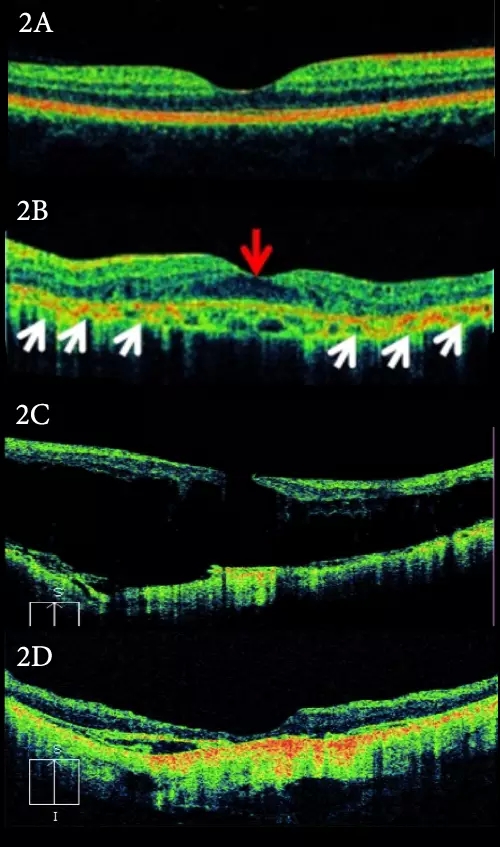

随着影像技术的发展,现时高解析度的光学相干断层扫描(Optical Coherence Tomography)也开始更多地被广泛应用在BCR的诊断中(图2)。

图2:图2A是正常的眼底黄斑OCT扫描。图2B是Bietti结晶视网膜病变的OCT扫描,可见黄斑中心凹下的视网膜色素上皮层的不连续(白色箭头),并伴有黄斑区水肿 (红色箭头) 。图2C的病人患上并发黄斑裂孔 (Macular Hole) 及黄斑视网膜脱离 (Macular Detachment) ;图2D是手术后的OCT,已把黄斑裂孔及黄斑视网膜脱离皆修补好。